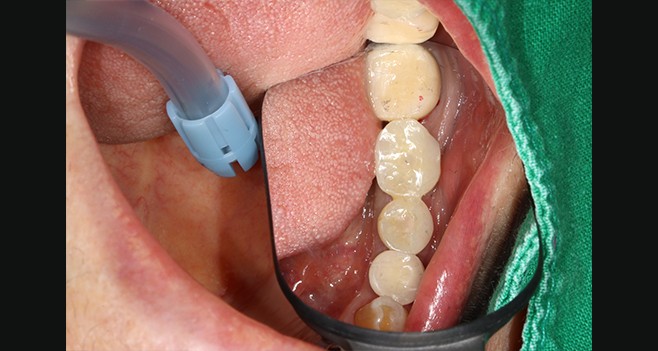

커스텀 어버트먼트에 완벽한 적합도를 확인할수있음 (3번 사진 참고)

커스텀 장착

커스텀 안착상태 페리사진